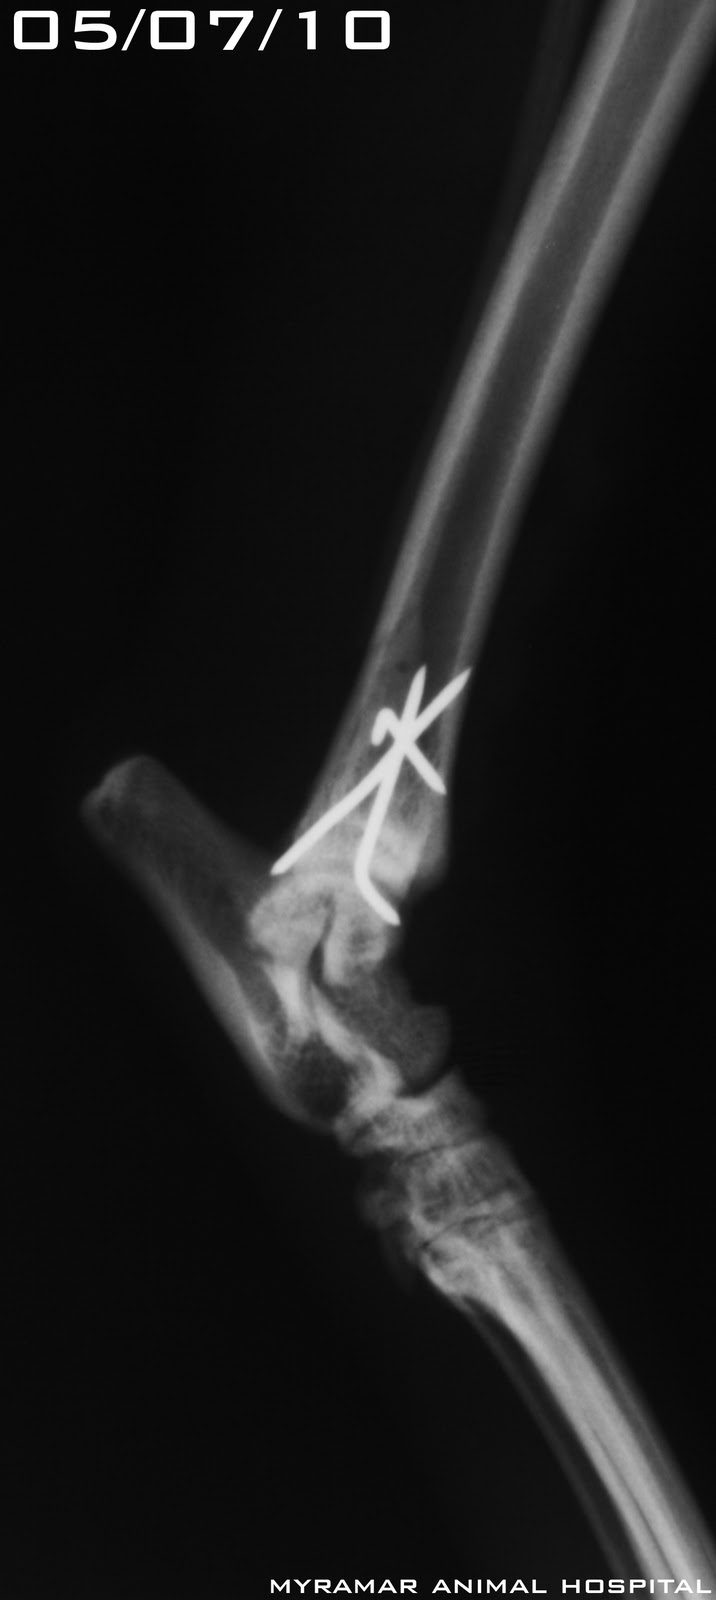

fractura bilateral tibial tras un accidente cuando volaba. Class AOVET:42-A3 y 42-B1. Ambas fracturas se reducen y estabilizan utilizando técnica Tie-in utilizando PMMA como conector de agujas.

Se presetan radiografías pre y postoperatorias así como evolución de la cicatrización ósea